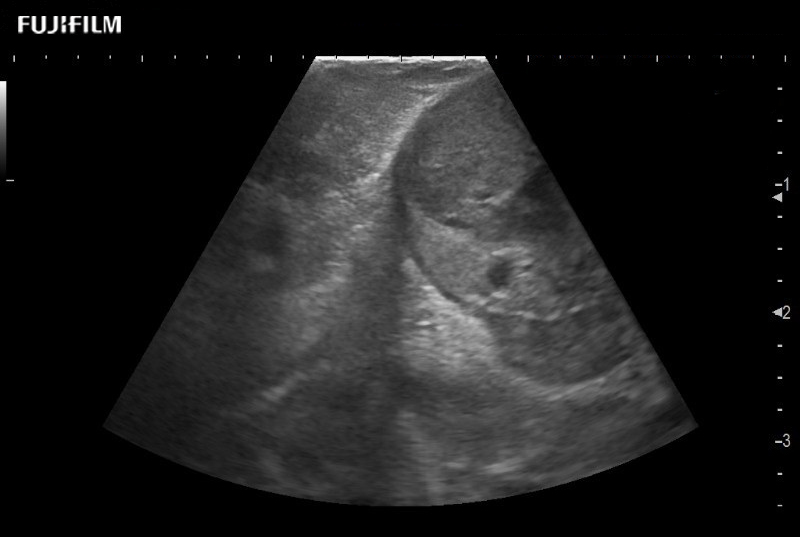

for use during robotic, laparoscopic and open surgical procedures: Tumor localization & staging, Ablation, Resection, Biopsy, Transplant, Abdominal exploration, Microsurgery

Curved array deep penetration “T” style finger-grip transducer for open surgical procedures.

Curved array 4-way laparoscopic transducer for better visualization of targeted lesions.

Exclusive linear array 4-way laparoscopic transducer for better visualization of targeted lesions.

Exclusive linear array rigid laparoscopic transducer for better visualization of targeted lesions.

Linear array side-fire “T” transducer for open surgical procedures.

Curved array “T” style finger-grip transducer for open surgical procedures.

Curved array deep penetration “I” style finger-grip transducer for open surgical procedures.

Exclusive linear array robotic surgery transducer.